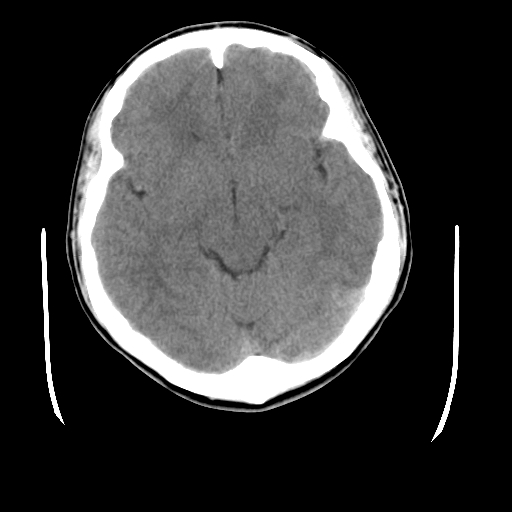

标题: CT23601:男, 17岁,剧烈头痛一小时。 [打印本页]

标题: CT23601:男, 17岁,剧烈头痛一小时。

男, 17岁,剧烈头痛一小时。

颅脑ct平扫颅内未见明确异常;剧烈头痛,建议必要时dsa造影。